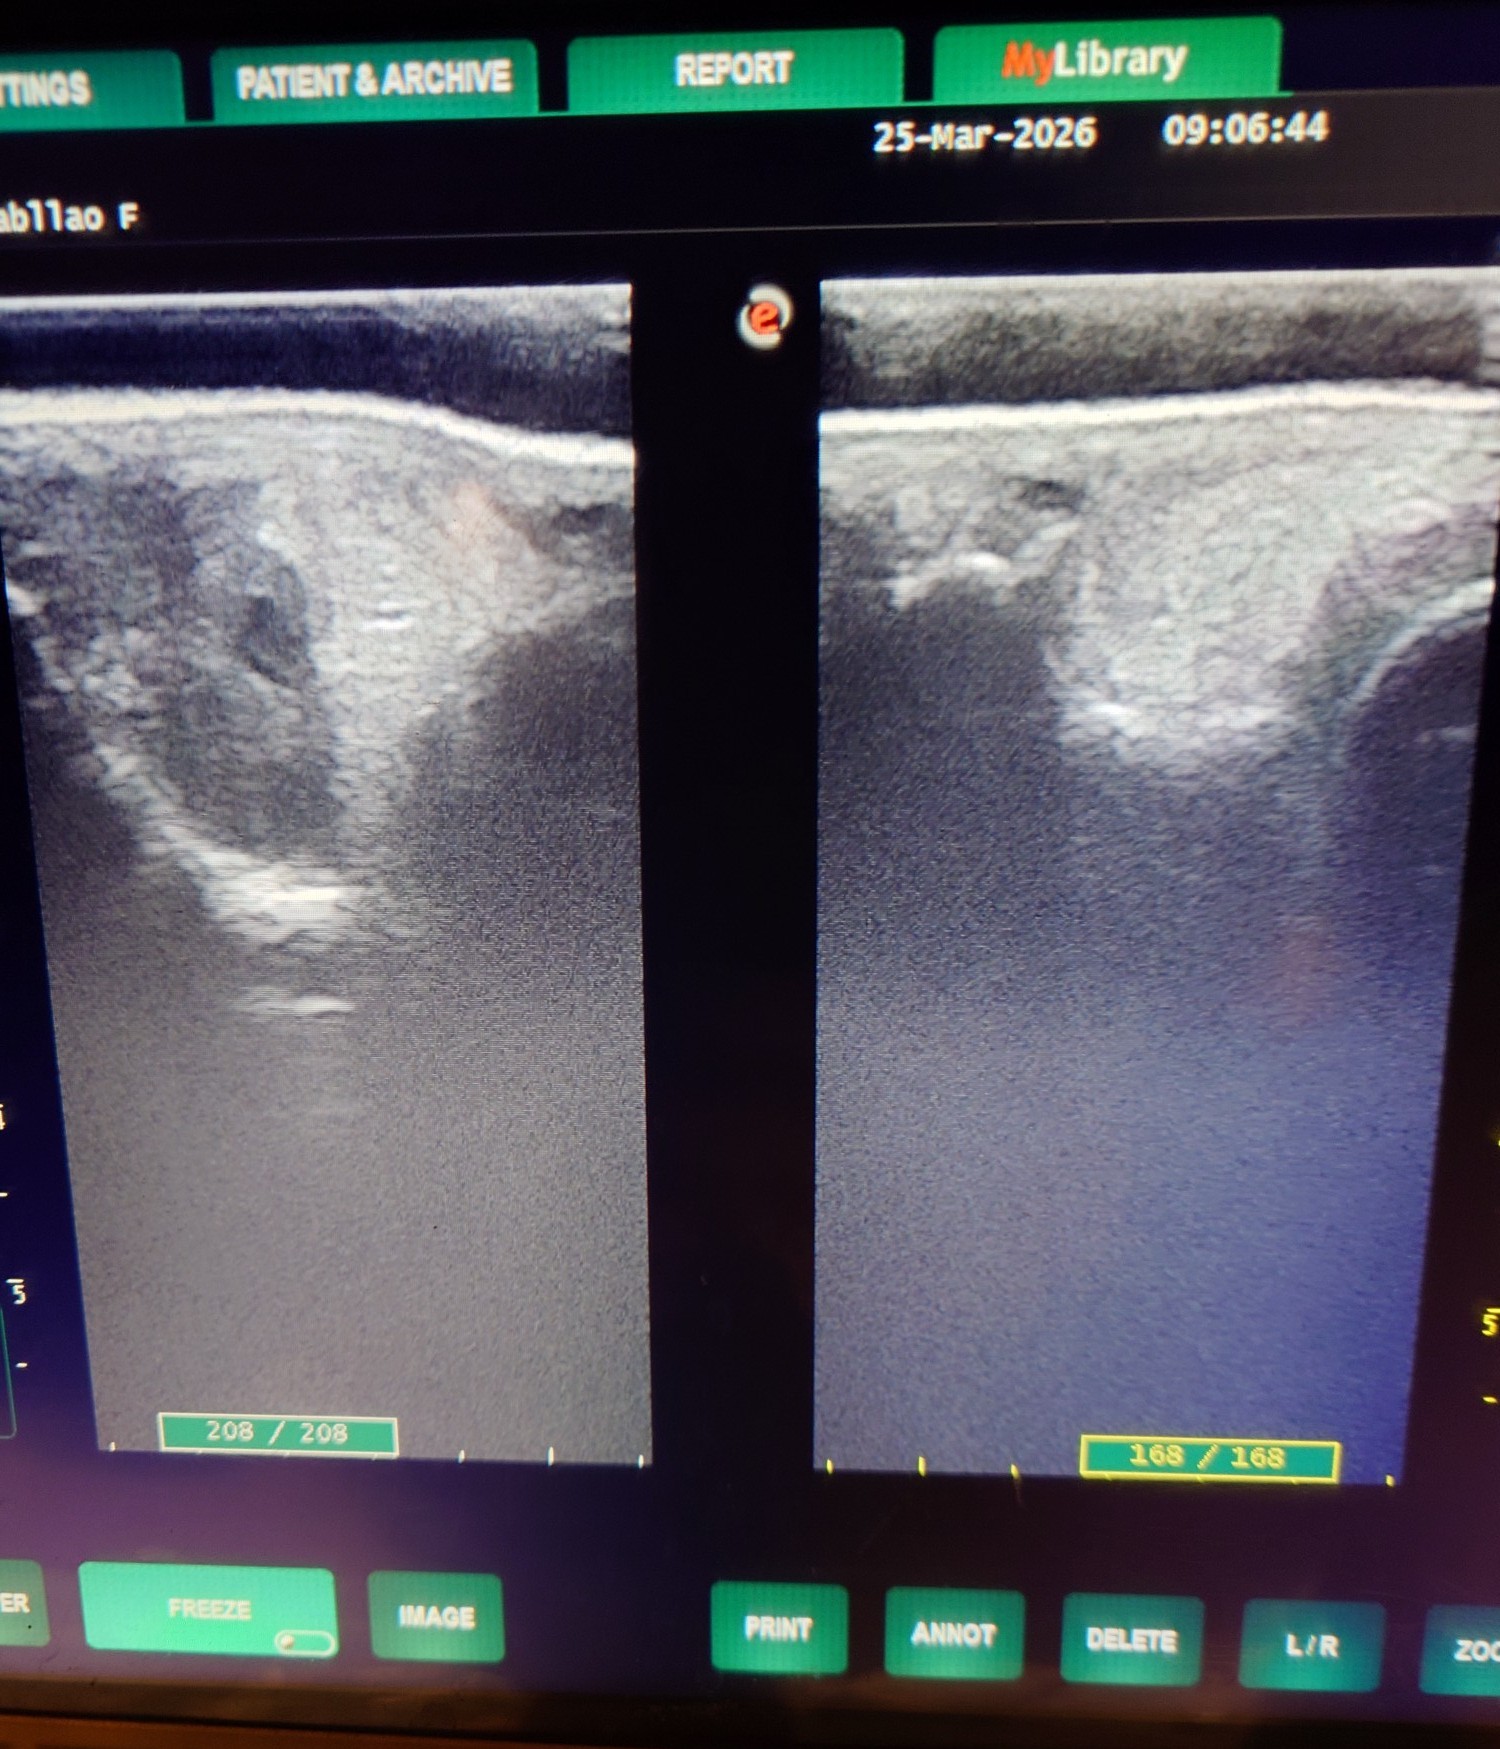

2012年にケンタッキーダービーを制した父アイルハヴアナザー産駒はアナザートゥルース(セン12歳)、オメガレインボー(牡10歳)他、タフなダート馬が多い。本馬は2歳時の6月に大井競馬場で新馬勝ちし、ハイセイコー記念6着後、3連勝で雲取賞へ臨み3着。羽田盃、東京ダービー後、休養して秋はA2B1クラスで出走しましたが惨敗が続いたため4歳時の2月28日に去勢。その後も結果を出せませんでしたが、5歳の8月にライアンクアトロ騎手が跨って快勝。そこからコンスタントに出走してA2(JRA交流2勝)クラスの特別戦で4勝を挙げました。8歳になった今年の3月の川崎戦で8着後、左前脚の球節が腫れてしまい、レントゲン検査で骨膜を発症していることが判明しました。剥がれかかっており、獣医師から全治3~4カ月と診断されたため現役を断念、引退することになりました。